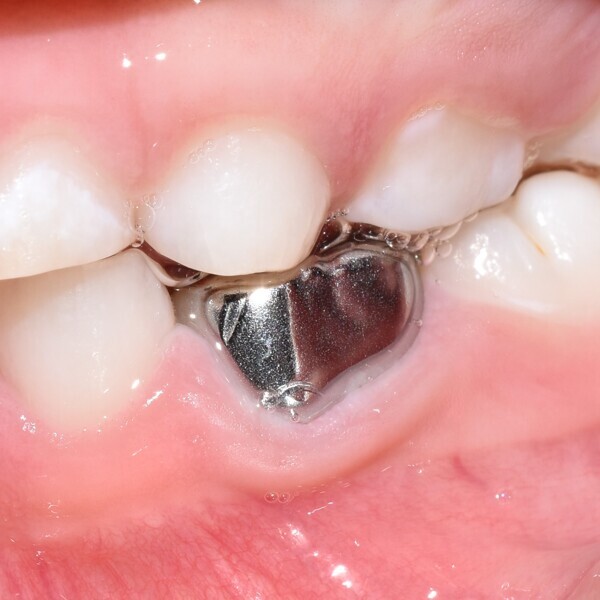

• Un second rendez-vous a été fixé 15 jours plus tard, afin de confirmer l’absence de signes ou de symptômes pathologiques, et la dent a été restaurée par une couronne en acier inoxydable qui a été scellée avec un verre ionomère, préparé à partir d’un mélange poudre-liquide (Ketac Cem Easymix).

Ce patient âgé de 6 ans et 7 mois présentait une carie dentaire à un stade avancé sur la première molaire temporaire inférieure gauche, sans aucun symptôme de douleur. La percussion et la palpation du versant vestibulaire de la gencive occasionnaient une légère gêne. Un abcès était présent, mais aucune mobilité dentaire n’était observée. La radiographie a révélé une zone importante de perte osseuse inter-radiculaire. Un diagnostic de nécrose pulpaire et d’abcès apical asymptomatique a été établi. Une pulpectomie a été réalisée et, au cours d’un second rendez-vous qui a permis de confirmer l’absence de signes ou de symptômes pathologiques, une couronne en acier inoxydable a été mise en place. La visite de rappel effectuée à 14 mois a montré l’absence de toute pathologie clinique et l’évolution normale du processus éruptif des prémolaires permanentes, malgré l’extrusion du matériau d’obturation.

Ce patient âgé de 7 ans présentait une douleur légère depuis plusieurs jours. L’examen a montré une lésion cavitaire étendue et profonde dans la première molaire temporaire inférieure gauche. La gencive ne présentait aucun gonflement, mais la dent était douloureuse à la percussion. La radiographie a confirmé la gravité de la carie, mais n’a révélé aucun signe correspondant à une modification de l’os environnant. Une pulpectomie était le traitement de choix. Le diagnostic de nécrose pulpaire a été confirmé après la préparation de la cavité d’accès et l’identification de trois canaux qui ont alors été complètement négociés.Lors d’un second rendez-vous, 15 jours plus tard, la dent était totalement asymptomatique et elle a été restaurée au moyen d’une couronne en acier inoxydable. À la visite de suivi à 36 mois, la dent présentait une fonction normale et était totalement saine.